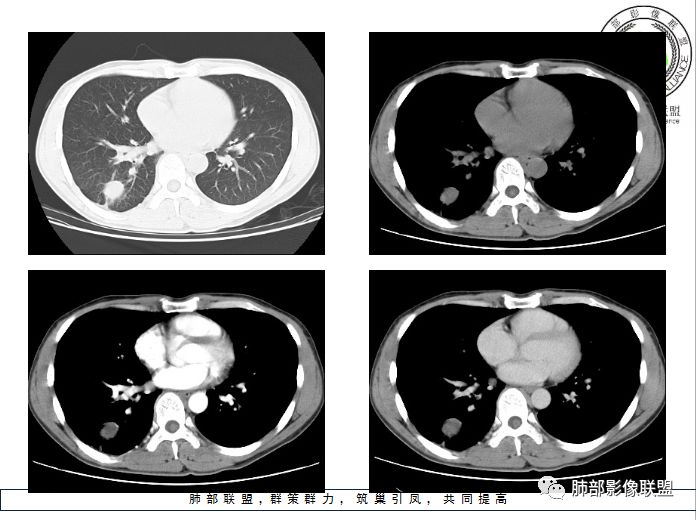

结果

晨读病理

支气管囊肿伴感染

小结

肺内支气管囊肿并感染一般都是囊腔内的感染,这个病例感染灶延续到远端,还伴有肺气肿;猜测是病变压迫近邻支气管造成的慢性炎症;病变以远的肺气肿,或许是活瓣效应。

肺内型支气管囊肿: 在单个肺段,支气管囊肿与支气管闭锁的鉴别比较困难。支气管囊肿应包括支气管闭锁形成的黏液囊肿,因为他们在病理结构上是一样的。但支气管囊肿多不形成周围的肺气肿。支气管闭锁在病理上也常报告为支气管囊肿:因为标本时常垂直于支气管长轴,造成对闭锁段判断困难,闭锁周围的肺组织多不含炭末。但影像上表现的支气管黏液囊肿和周围肺气肿改变可确定先天性支气管闭锁的诊断。